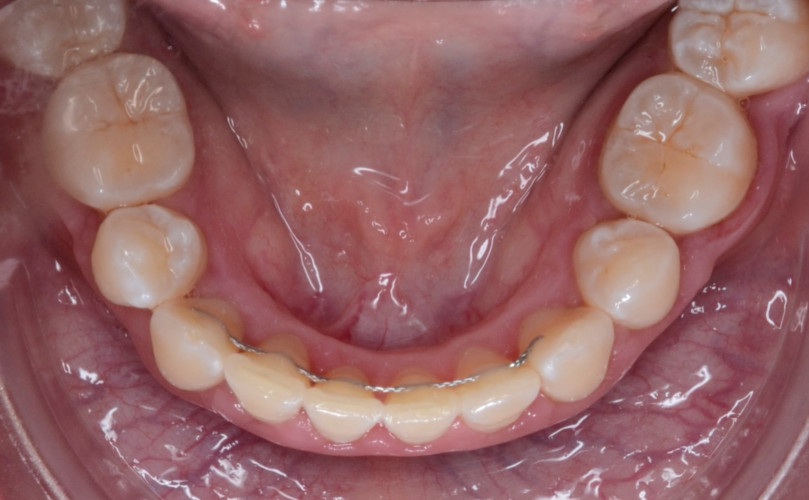

Caso de Ortodoncia con Brackts

La ortodoncia no es estética. La ortodoncia es sinónimo de salud. En ocasiones existe tanta falta de espacio que el apiñamiento impide realizar una...